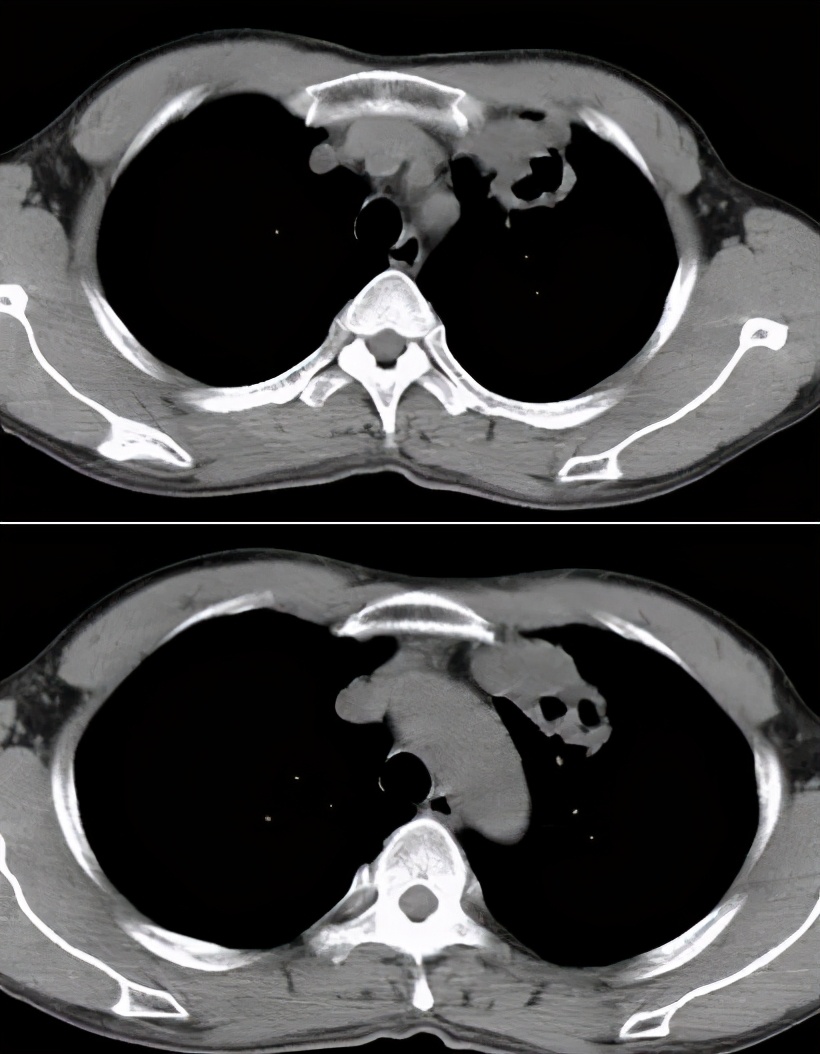

病例4:

男性,26岁。2015年8月入院,因「咳嗽、咳痰一个半月,胸痛半月,加重伴高热一天」入院。 糖尿病病史8年余,平素血糖控制差,入院时尿酮体+++。

(一个半月前无明显诱因下出现咳嗽、咳痰,起初为白色泡沫痰,后逐渐转为黄绿痰,量逐渐增多,咳嗽为阵发性,夜间为著,并半伴有盗汗明显,当时无发热,无明显胸闷、气喘,一直未予以重视,未服用药物治疗,半月前患者出现胸痛,以右侧为著,为持续性痛,深呼吸及右侧卧位时胸痛明显,有肩背部放射痛,后患者胸痛症状逐渐加重,并逐渐出现胸闷、气促,今日患者出现发热,体温可达40.0℃,伴有畏寒和怕冷,自觉胸痛症状明显加重,全身乏力,胸闷、气促症状明显,无心前区不适,遂就诊我院急诊,查胸部CT提示右侧液气胸,压缩约99%;右肺萎陷不张,伴可疑空洞及气液平。为进一步诊治,收入我科。精神萎,胃纳欠佳,夜间睡眠欠佳,近期体重无明显改变。

查体:体温:38.0℃ 脉搏:112次/分 呼吸:30次/分 血压:114/65mmHg 吸氧下指末氧 96%。神清,呼吸急促,精神萎。浅表淋巴结未及肿大。右上肺叩诊呈鼓音,右下肺叩诊呈浊音,右肺呼吸音消失,左肺听诊呼吸音清,未及干湿啰音。心律齐未及杂音。腹平软无压痛未及肝脾肿块。下肢无明显水肿。病理反射未引出。)

最终痰涂片找到抗酸杆菌1+。

图:胸部CT:右侧液气胸,右肺实变,伴空洞及气液平。